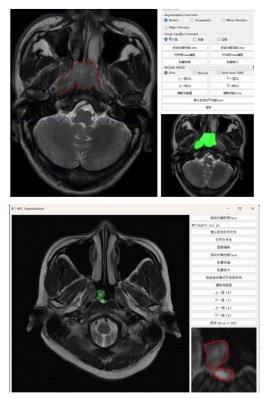

4. AI赋能医学影像分析

针对鼻咽癌等华南地区高发的肿瘤影像自动化分析的需要,学院智能医学影像分析团队致力于攻克研究医学影像中目标自动或半自动化的完整勾画方案。利用深度学习的方法攻克了影像中模糊边界的目标分割方法,相比传统方法的分割性能提升了25%。基于大模型技术研制了鼻咽癌半自动完整勾画软件系统。目前,该软件应用于中山大学肿瘤防治中心的头颈部MRI影像的鼻咽癌筛查工作中,大大地减轻了医生对目标勾画的工作量。

图5. 鼻咽癌影像筛查系统